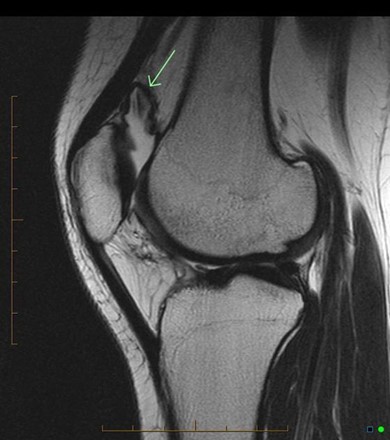

Synovial Plica

A benign embryologic remnant, this condition has a prevalence of up to 50%. It commonly presents as chronic pain with intermittent “locking” or “catching” of the joint in adolescents and athletes. It most commonly is associated with flexion-extension movements, but why some people develop significant symptoms when the prevalence is so high in the general population remains unclear. MRI, while not necessary, typically reveals the remnant. Conservative management is indicated for most patients and consists of analgesics, NSAIDs, and PT. Efficacy varies widely in the literature, with reports as low as 40% and as high as 87%. Operative management to resect the structure is indicated for individuals with recalcitrant pain.

This is an MRI diagnosis and is best appreciated with the full set of images

Case courtesy of Dr. Andrew Dixon, Radiopaedia.org. From the case rID: 41239